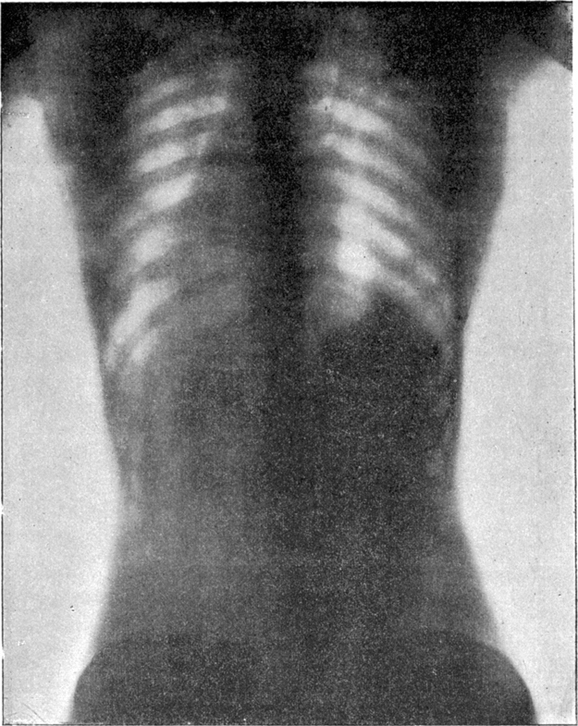

Hình ảnh chụp X-quang của người không mặc áo corset (trên) và người mặc chiếc áo thu nhỏ eo này (dưới).

Tuy nhiên, loại áo này thực sự là con dao hai lưỡi. Bên cạnh việc thu gọn vòng eo, áo corset đã cắt đứt mọi lưu thông giữa đầu và chân của người mặc khiến phụ nữ nghẹt thở, gẫy xương sườn và có thể dẫn đến xuất huyết nội tạng.